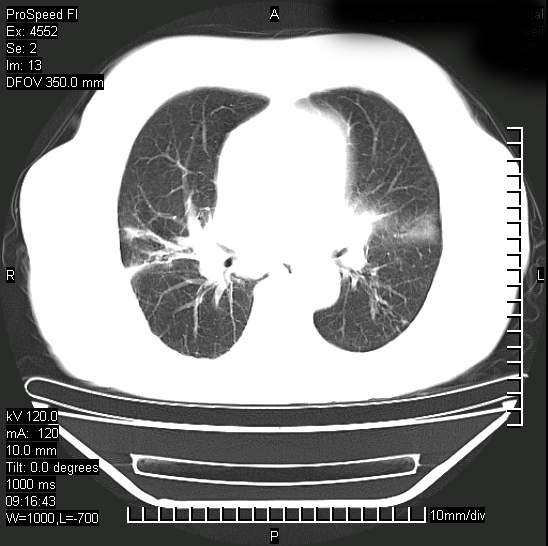

今天ct

支持陈旧性肺结核并两下肺感染,两侧胸腔积液。

支持  结核ban感染,节段性肺不张,支气管内膜结核可能

继发性结核感染加重。左侧合并有支气管内膜结核。

1)两肺结核并感染。2)不排除左肺上叶中央型肺癌并阻塞性肺炎、肺不张可能;建议行纤支镜检查。3)右肺门及纵隔淋巴结肿大。4)双侧胸腔积液。